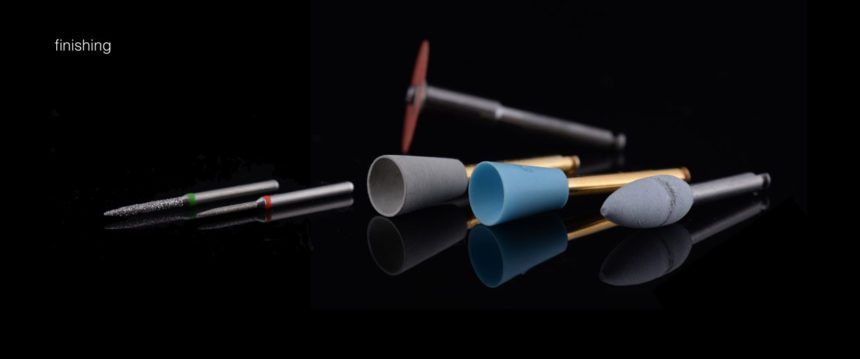

Θα αφιερωθεί αρκετός χρόνος και αρκετή προσπάθεια στις πολύ σημαντικές διαδικασίες λείανσης και στίλβωσης.

- Θα αφιερωθεί αρκετός χρόνος και αρκετή προσπάθεια στις πολύ σημαντικές διαδικασίες λείανσης και στίλβωσης.